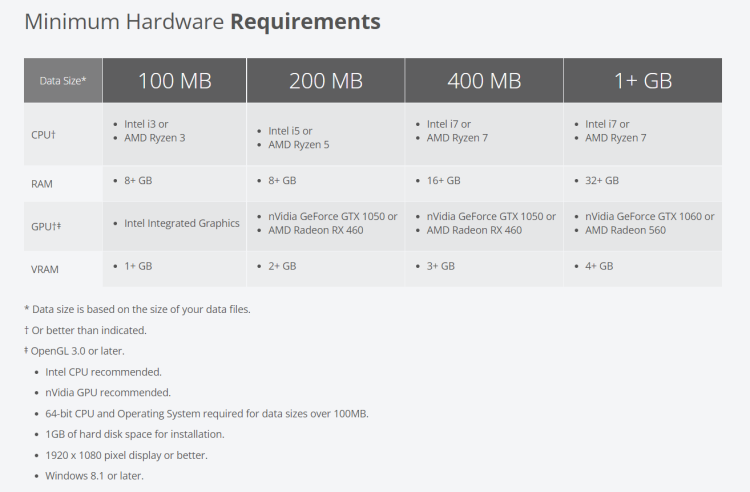

Pro Surgical 3D

Description

View X-Ray CT & MRI Scans Fast and Easily

FREE and easy to use 3D DICOM Viewer – for surgeons and patient education

Designed for surgeons, Pro Surgical 3D makes it easy to view patient scans quickly. Pro Surgical 3D facilitates the optimal 3D treatment and assessment workflows based on X-ray CT and MRI scans – and best of all, it’s FREE!